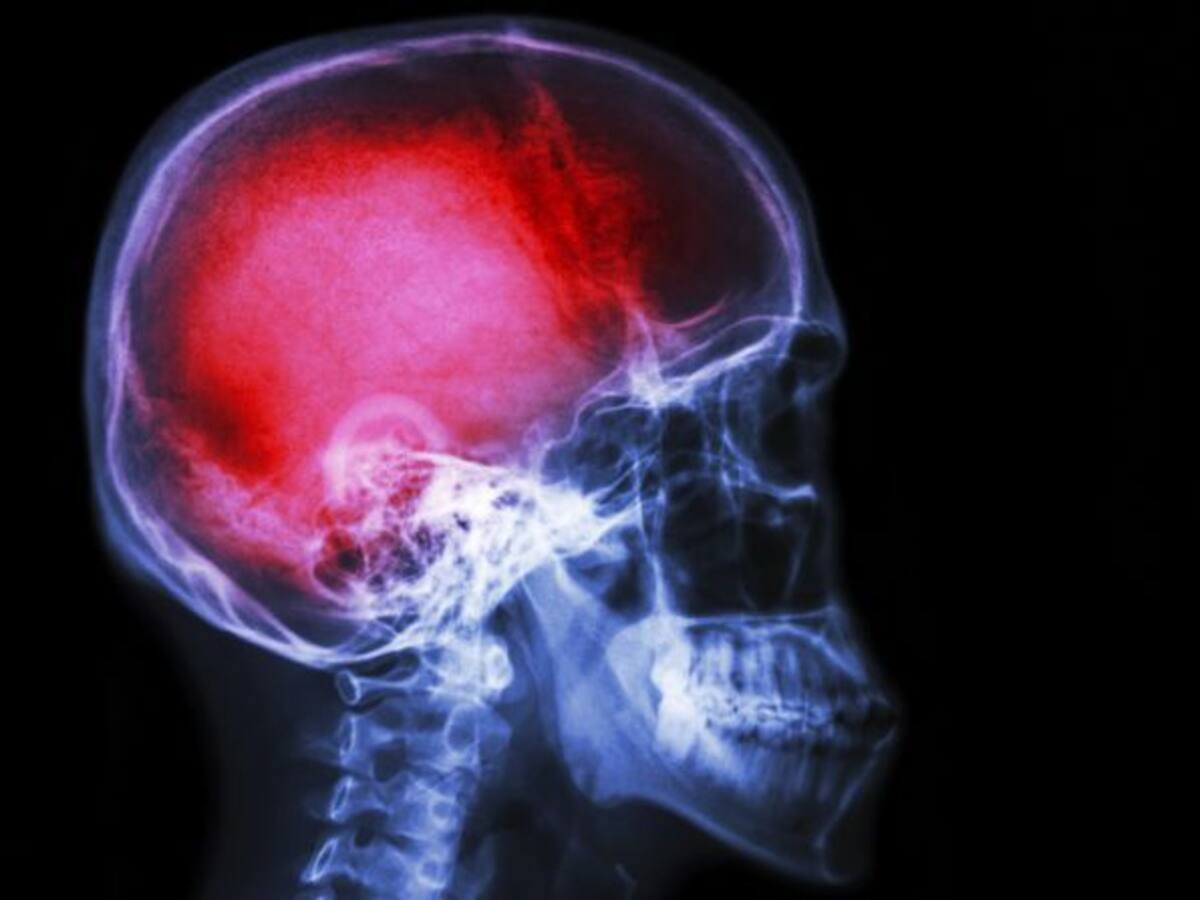

La mitad de los menores de 40 años que sufren un ictus han consumido cocaína